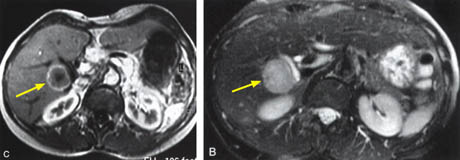

![]() |

The Liver, Kidney

and Small Intestine

|

Figure 8.

Figure 8a-8d.

Further examples of the exceptional anatomic detail

made visible by the DISCOVERY

of Damadian of the pronounced differences in the decay

rates (relaxations) of the NMR signals

of the body's normal tissues (Figure

6). The DISCOVERED

differences supply the pixel amplitude differences

"PIXEL CONTRAST (IMAGE DETAIL)"

that produce, for the first time in medical history,

the detailed visualization of normal human anatomy

MRI is noted for. Note the visualization of the

vestibular and cochlear nerves

WITHIN

the internal auditory canel (Figure 8b) and the visualization

of the hypothalamic

tract (that transports hormones from

the brain) WITHIN

the pituitary stalk. (Figure 8c)